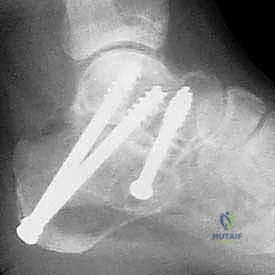

- دمج المفصل تحت الكاحل (Subtalar Arthrodesis):

في الغالبية العظمى من حالات سوء الالتئام، يكون المفصل تحت الكاحل قد تدمر تماماً بسبب الخشونة والاحتكاك. الحل الجذري والنهائي للألم هنا هو "دمج" أو "تثبيت" هذا المفصل. يقوم الدكتور هطيف بتنظيف الغضاريف التالفة بالكامل، ووضع العظام في وضعها التشريحي الصحيح، ثم تثبيتها باستخدام براغي معدنية قوية جداً (Screws) لتلتحم وتصبح عظمة واحدة صلبة خالية من الألم.